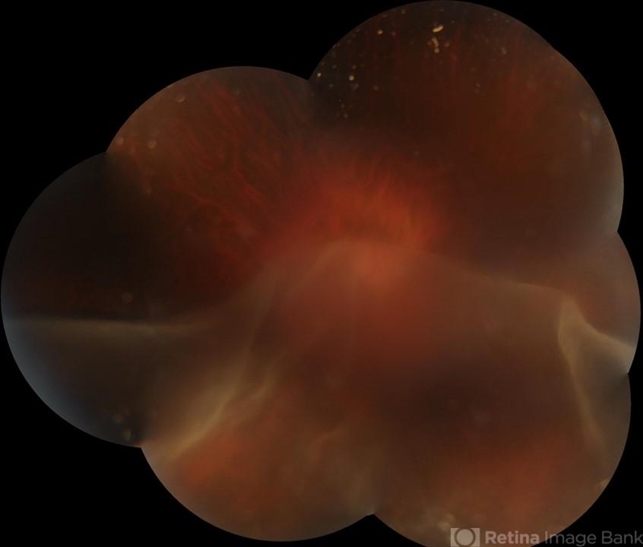

- GIANT RETINAL TEAR

- HIGH MYOPE WITH A CORRECTION OF -24D. SUDDEN VISION LOSS FOLLOWING TRAUMA. SUPERIOR RETINA FOLDED ON TO THE INFERIOR RETINA MASKING THE DISC IN A TRANSLUCENT VEIL.